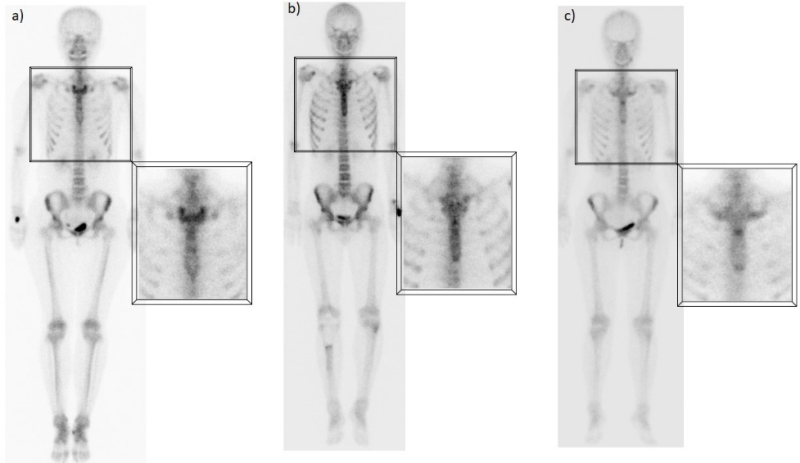

E) Captación esternal

Generalmente este hallazgo se atribuye a cambios degenerativos de las articulaciones esternoclaviculares, bastante frecuentes y que aumentan con la edad, ya que se trata de articulaciones sinoviales que soportan un estrés constante(10). Sin embargo, algunos estudios han descrito patrones de captación normales específicos en el esternón, relacionados con la edad, que no necesariamente representan cambios articulares. Los hallazgos sugieren que una captación difusa, homogénea y leve es normal en pacientes jóvenes, mientras que un patrón más heterogéneo y segmentario, con mayor actividad en los bordes óseos, también puede ser completamente normal en pacientes de edad avanzada(11). Asimismo, la captación focal a nivel de la articulación manubrio-esternal o ángulo de Louis es un hallazgo frecuente, independientemente de la edad, que en la mayoría de los casos puede explicarse por la osificación a nivel de la sínfisis o la presencia de crestas óseas (fig. 5).